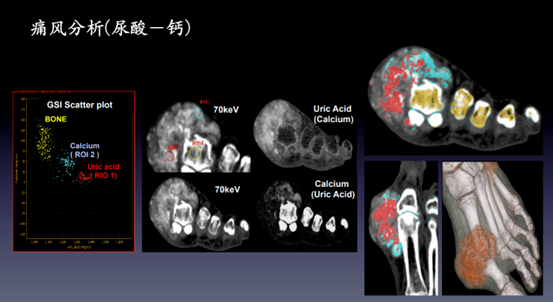

3、痛风检查:看清“尿酸结晶”,告别模糊诊断。

发现更早:识别常规CT/DR难以显示的1 mm尿酸结晶,提前预警痛风石形成。 评估更准:精准量化结晶体积与成分(尿酸绿 vs 钙盐紫),判断降尿酸药是否“溶晶”成功,医生据此即时调整剂量或换药,避免无效长期用药。